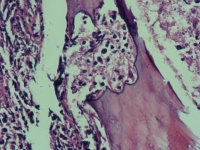

性别

男

年龄

74岁

腰骶部疼痛不适2月余 CT示骶髂处溶骨性改变伴周围软组织肿胀

骶髂处骨组织活检

1*1*0.5cm灰红碎组织

建议:CK;EMA;S-100等,排除脊髓瘤的可能性!(CT诊断什么?)

浆细胞性骨髓瘤或髓系肿瘤应考虑……